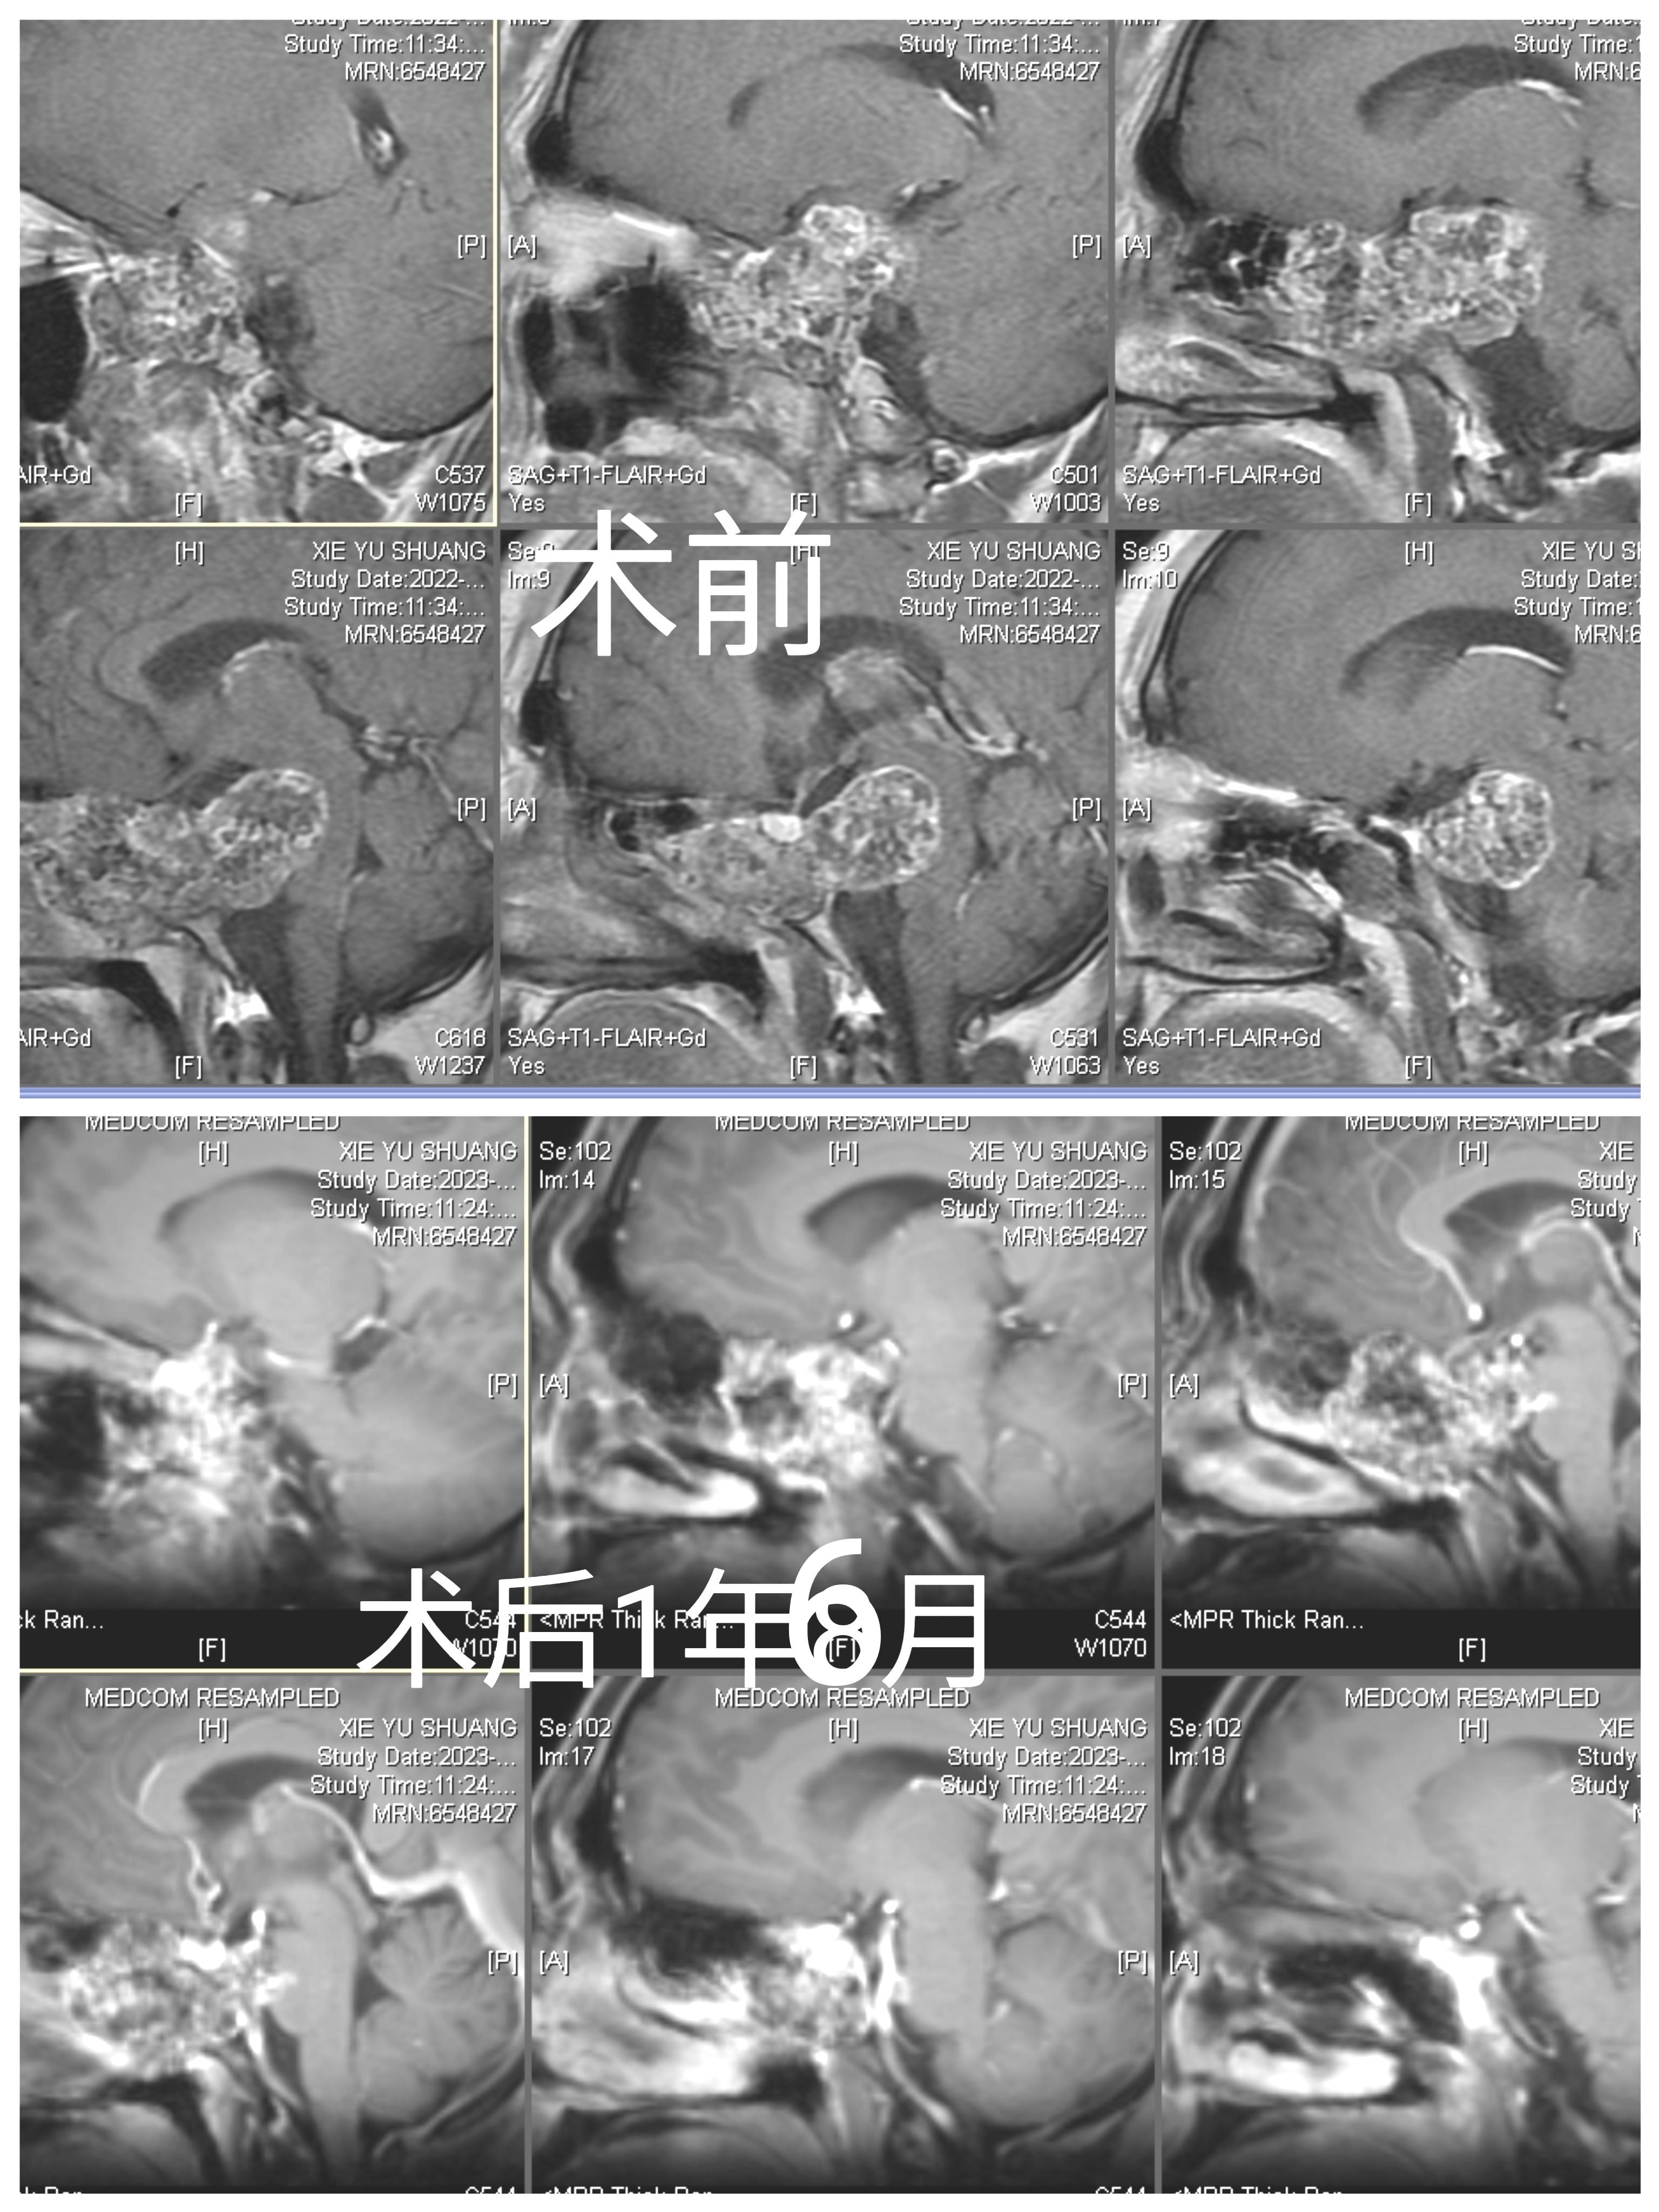

手术前

手术后